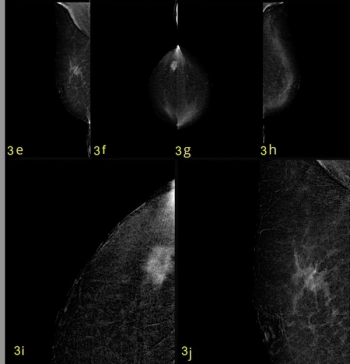

New research showed a 96 to 97 percent sensitivity for contrast-enhanced mammography (CEM) with an increased iodine delivery rate facilitating robust contrast enhancement for women with aggressive breast cancer.